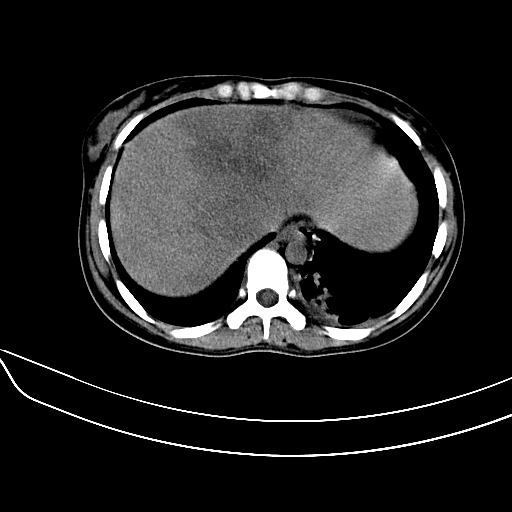

标题: CT7307:糖尿病引起的肝、脾损害?

女,22岁,临床以糖尿病等病史入院,两年前有妊娠合并胰腺炎史,现有多饮、多尿、咳嗽、咳痰、左腰痛、发热等。因多种原因没做增强。

图象发的太少,第二幅图肝左内叶低密度影中似有更低密度影,建议强化.

考虑:1、不均匀性脂肪肝(肝大+不均质密度);